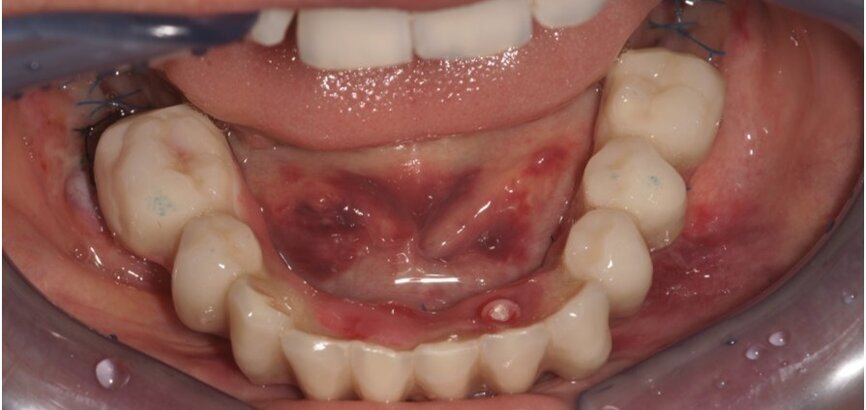

Dn. 18.09.2013 r. w znieczuleniu przewodowym zostały usunięte wszystkie zęby. Celem dokładnego usunięcia ziarniny przed ekstrakcją wykonano ucięcie wg Widmanna (Ryc. 3). Jednym z warunków powodzenia zabiegu jest dokładne usunięcie zmienionych chorobowo tkanek miękkich tak, by pozostawić zdrowe.

Implanty zostały wprowadzone wg zasady przylegania w cieniu, tzn. wszczep musi na całej swojej długości mieć kontakt z którąś ze ścian zębodołu 1-2 mm subkrestalnie (Ryc. 4). W przypadku konieczności użycia membrany, musi ona mieć możliwość rozpostarcia się nad ubytkiem kostnym i implantem tak, aby odległość pomiędzy membraną a wszczepem nie była mniejsza niż 2 m (Ryc. 3). Wszczepy o